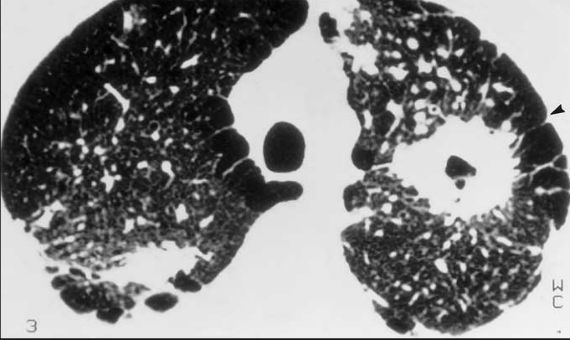

Las muertes y enfermedades que ocurren entre los trabajadores que limpian con chorros de arena o que perforan rocas son indicadoras de la gravedad de los riesgos de salud asociados con la exposición a la sílice. El hecho de respirar el polvo de sílice cristalina puede causar silicosis, que en sus aspectos más severos puede resultar en la discapacidad o la muerte. El polvo de sílice respirable entra en los pulmones y crea la formación de tejido de cicatriz reduciendo la capacidad de absorción de oxígeno por los pulmones. La silicosis no tiene cura. Dado que afecta el funcionamiento de los pulmones, uno es más susceptible de contraer infecciones pulmonares como la tuberculosis.